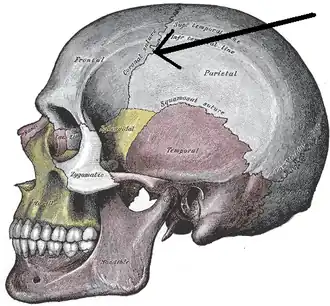

Anterolateral view of coronal suture (red) | |

Side view of the skull. ('Coronal suture' indicated by the arrow.)

Side view of the skull. ('Coronal suture' indicated by the arrow.) -